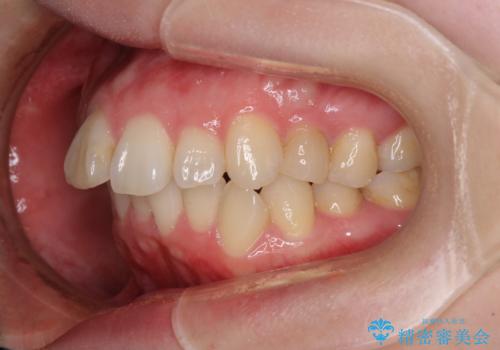

口元の閉じにくさを改善するためには、上顎臼歯を後方に移動させた咬み合わせにする必要があります。

インビザライン単体で改善することも可能ですが、達成する可能性が高くないため、カリエールディスタライザーという補助装置を併用して、より確実性を上げることとしました。

奥歯の咬み合わせを改善しながら、並行してインビザラインで歯列を整えることとしました。

カリエール・ディスタライザーを用いたことで上顎前歯の突出感はスムーズに解消され、歯列不正は1年半ほどでほぼ改善することができました。

しかし、その後インビザライン特有の奥歯がうまく噛めないという問題が長引き、改善に1年近い期間を要することとなりました。